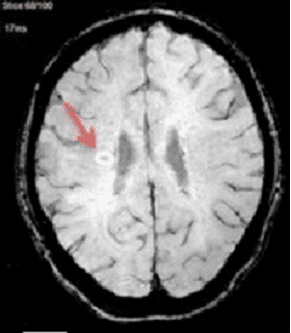

Central vein sign (CVS) – MS lesions in the brain are often centered around tiny veins, a feature known as the CVS. This sign can be clearly seen with certain MRI techniques.  Research has demonstrated that using the CVS for diagnosis is highly effective, with a large study underway to further confirm its value in clinical settings. Because CVS is specific to MS, it is a way to distinguish MS from other neurological diseases that may look similar, such as migraines or small vessel disease. Although it doesn’t differentiate between types of MS, the CVS is a promising tool for diagnosing the disease and could soon become a regular part of how doctors identify MS in patients.

brain MRI image

Image from https://www.sciencedirect.com/science/article/pii/S0378603X17301596

Paramagnetic Rim Lesions (PRL) – In MS, some brain lesions stay active, even after the initial inflammation subsides and can turn into chronic active lesions (CAL).  These areas can grow slowly, contributing to the worsening of MS over time.  CALs can be identified on MRI because they often have a distinctive ring of iron around them. This ring is referred to as a PRL.  While not every person with MS has PRLs, research shows that when they are present, especially alongside CVS, they can help confirm the diagnosis.  In addition, a higher number of PRLs has been linked with more severe disability in MS, suggesting these lesions could be important for predicting how the disease might progress.